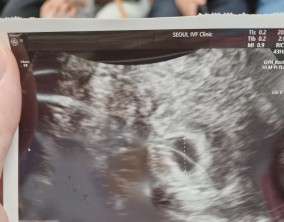

심장소리 이후, 함께 웃게 된 임밍아웃

유정원장님 치료 과정 내내 항상 따뜻하게 진료해 주셔서 감사한 마음이 큽니다. 덕분에 불안한 순간에도 마음을 다잡고 치료를 이어갈 수 있었습니다.